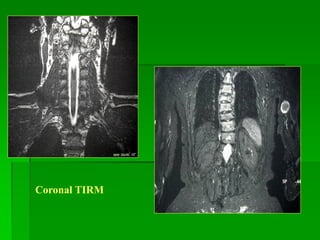

Coronal TIRM

Sagittal T1W Sagittal T2W

Sag T1W Sag T2W Sag TIRM